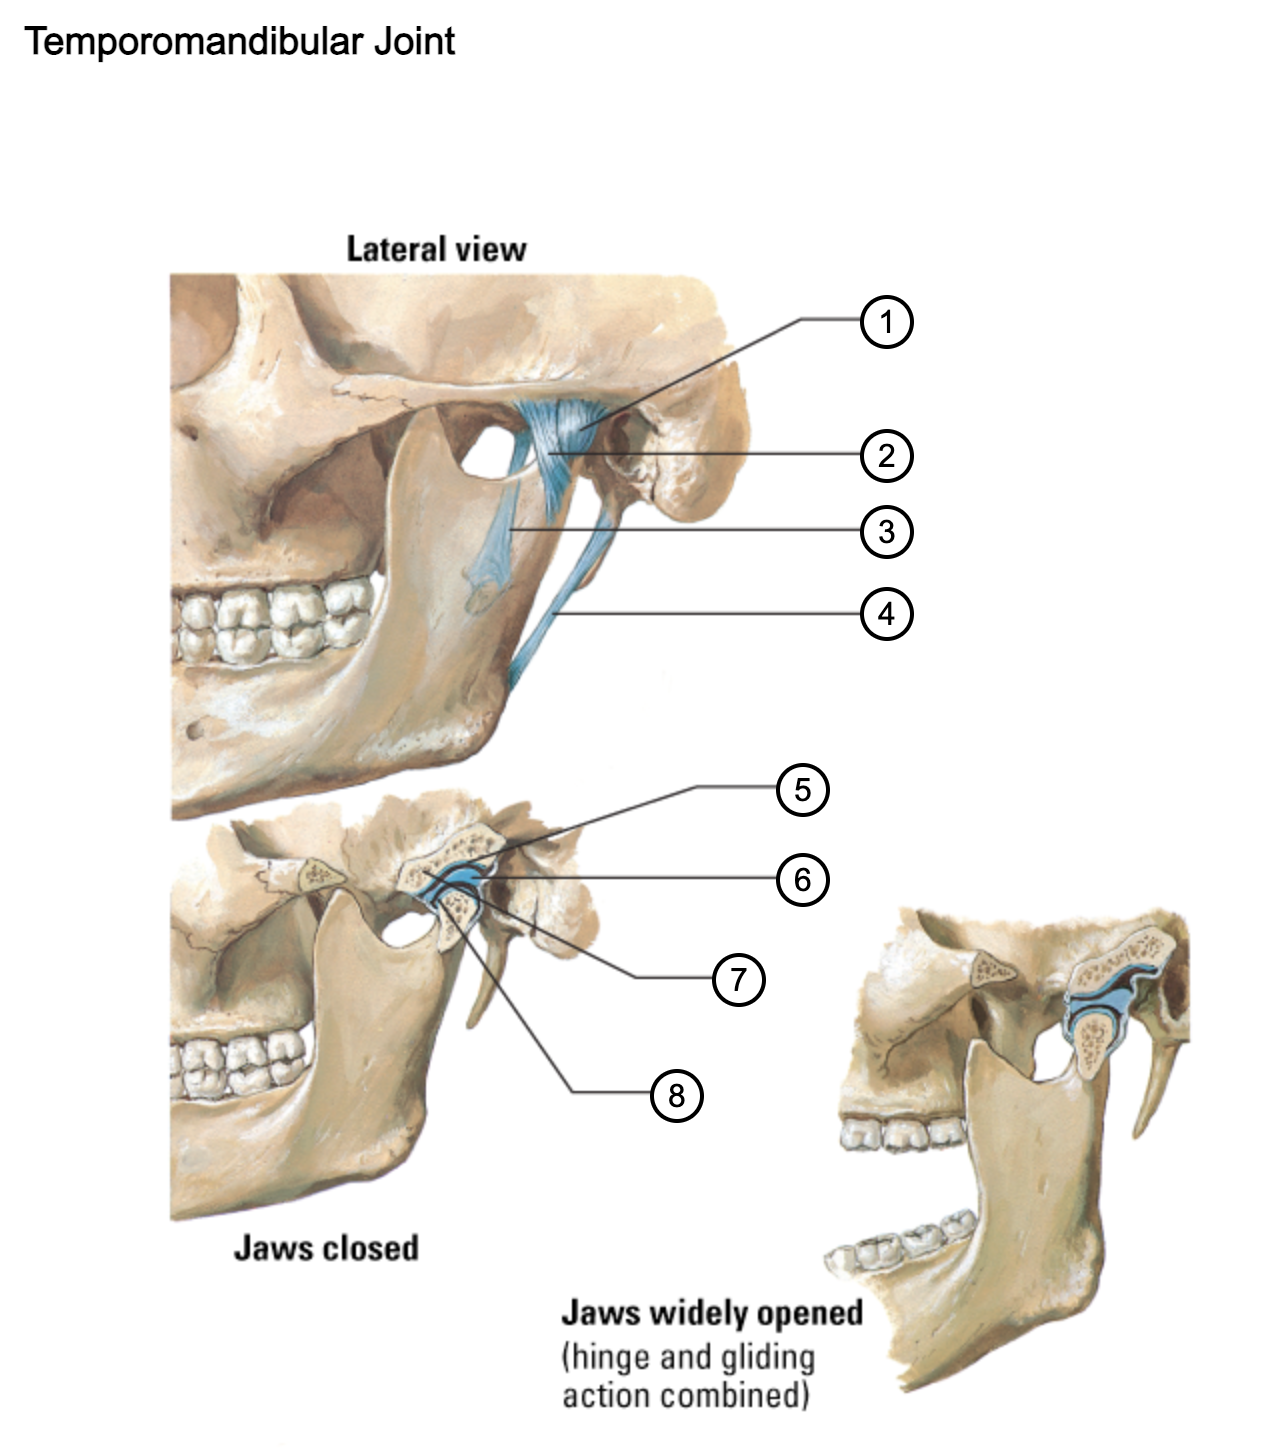

1

capsule of temporomandibular joint

2

lateral temporomandibular ligament

3

sphenomandibular ligament

4

stylomandibular ligament

5

mandibular fossa

6

articular disc

7

articular tubercle

8

capsule of temporomandibular joint